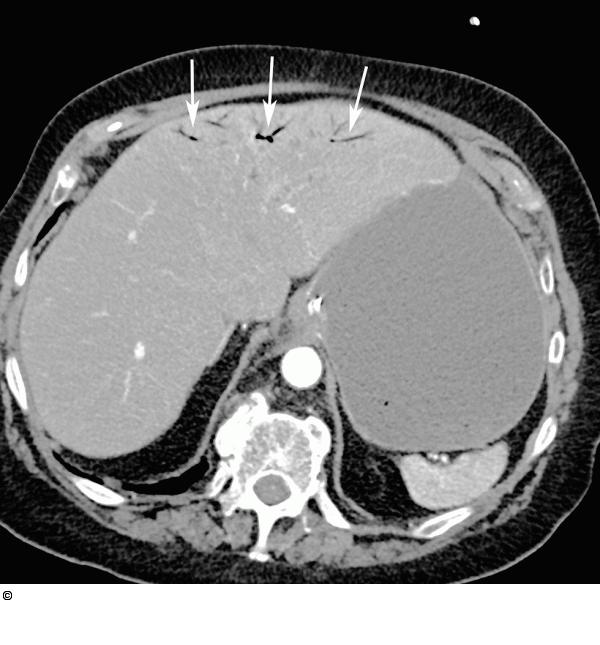

Abbildung 2: Intrahepatische Pfortaderäste Das axiale MDCT-Bild zeigt reichlich Luft in den intrahepatischen Pfortaderästen (Pfeile) als Folge der intestinalen Pneumatose. |

Das axiale MDCT-Bild zeigt reichlich Luft in den intrahepatischen Pfortaderästen (Pfeile) als Folge der intestinalen Pneumatose. |